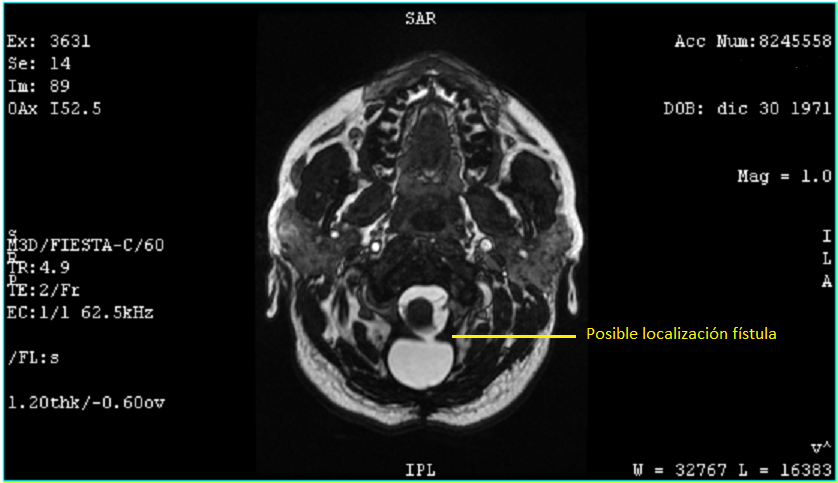

27 Julio 2020 4.1 x 3.0 x 1.6 cm y 11.04 centímetros cúbicos y un trayecto fistuloso de 0.7 cm.

El 6 de agosto regresé con los resultados de la resonancia, análisis de sangre y orina, esta vez yo tuve los resultados primero, así que al verlo lo primero que dije fue "¿Qué pasa doctor que mi cuerpo sigue rechazando el parche?", la resonancia confirmó lo mismo el quiste media 4.2 x 1.7 x 2.9 cm y 10 centímetros cúbicos y la fistula 4.8 mm y el remanente del tumor es de 15.1 mm, en contraste con en el ultrasonido 4.1 x 3.0 x 1.6 cm y 11.04 centímetros cúbicos y la fistula 0.7 cm.

Afortunadamente el doctor estaba de mejor humor, porque mientras veía los resultados me contestó "Su cuerpo es muy chocosito que quiere, esto no tiene nada que ver con las cirugías, de eso está perfecta", me mostró que el remanente del tumor alojado en el tallo cerebral y cree que mi falta de equilibrio y náuseas tienen que ver más eso. El tallo cerebral regula las funciones vitales lo que significa que mi falta de equilibrio será permanente, de las náuseas no lo sabe.

"El quiste no ejerce ninguna presión en cerebelo o tallo cerebral, y el resto está perfecto no hay ningún daño" "Supongo que algo tiene que hacer con la fístula, no me puedo quedar así o sí?", "Bueno, no representa peligro alguno, ya que es la misma agua circulante, pero vas a regresar al medicamento que reduce el líquido del cerebro, usa la venda en las noches para hacer presión, evita cualquier esfuerzo o cargar cosas pesadas, porque solo generaría presión, en un mes vienes y vemos si se redujo el quiste y cerró la fístula y evaluamos si te ponemos una válvula".